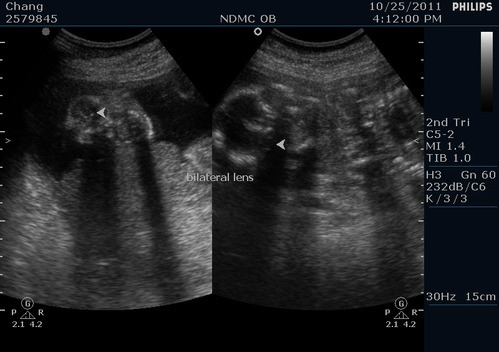

兩眼的眼距

左右眼的眼珠子